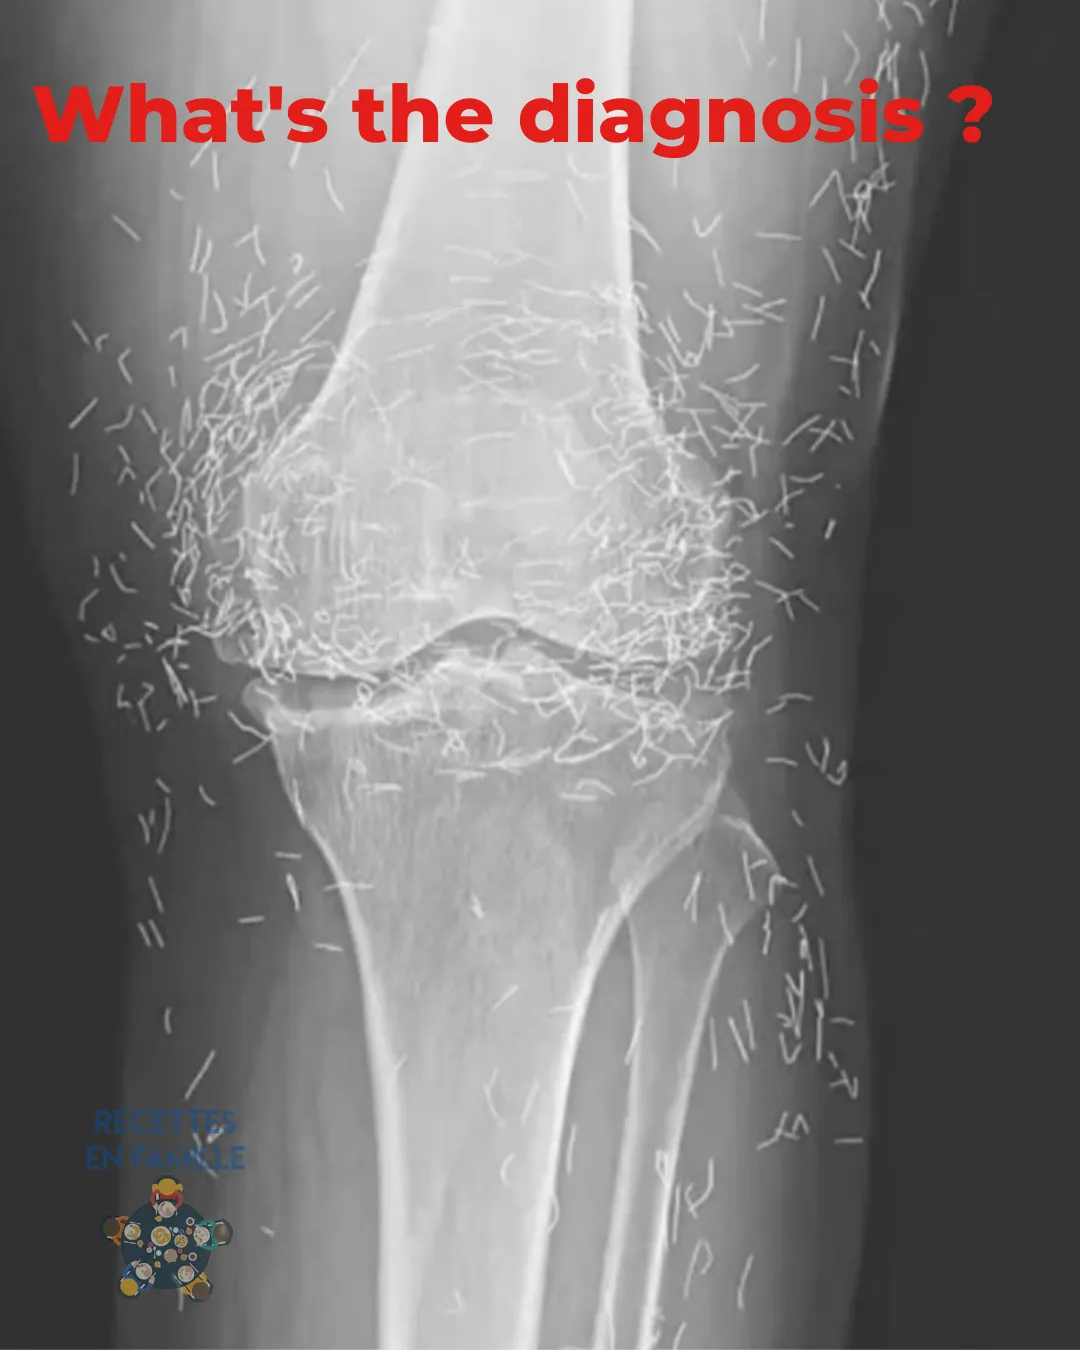

Des Aiguilles en Or Découvertes dans les Genoux d’une Femme

Imaginez aller chez le médecin pour des douleurs aux genoux… et découvrir quelque chose d’incroyable sur vos radiographies. C’est exactement ce qui est arrivé à une femme sud-coréenne âgée de 65 ans. Ses genoux étaient remplis… d’aiguilles en or ! Oui, vous avez bien lu : des centaines de minuscules aiguilles laissées dans ses tissus. Pourquoi … Read more